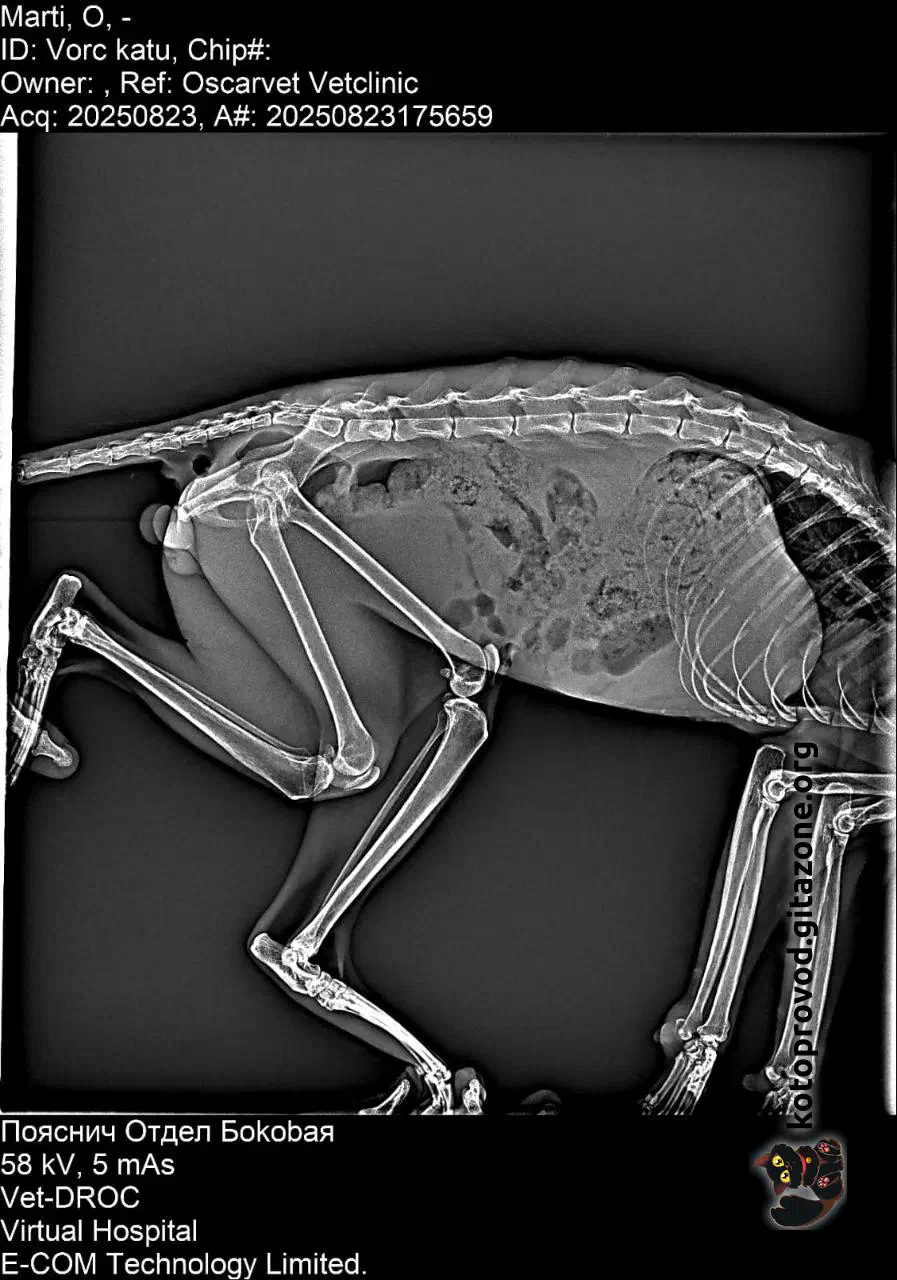

Мартини (бело-рыжий) — мальчик, возраст пока не понятен. Сдали анализы крови, сделали УЗИ — ясности с диагнозом пока нет. Есть несколько гипотез, одна хуже другой. Факты: поджелудочная, почки, печень — деформированы, нарушены структуры. Кровь по показателям намекает, что проблемы с кроветворением. Меньшее из всех его проблем — застарелая травма таза, из-за которой он с трудом передвигается. Вероятно, испытывает боль.

Рентген